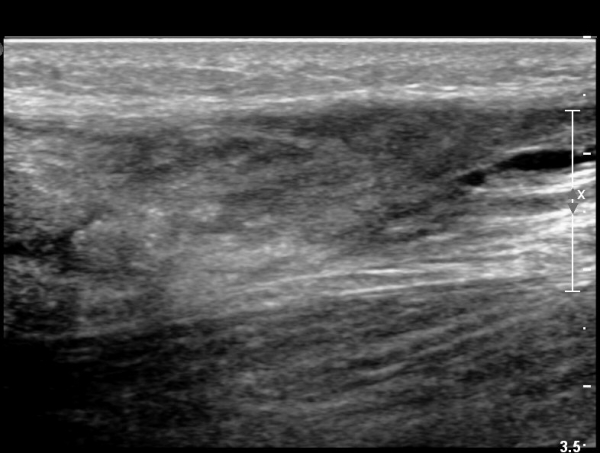

¾ÆÅ³·¹½º°Ç Àú¿¡ÄÚºÎÁ¾ÀÌ °¨¼ÒµÇ°í  ÆÄ¿­ºÎÀ§ Àú¿¡ÄÚ°¡ È£ÀüµÇ¾î

°ÇÀÇ ¼¶À¯¼º¾ç»ó(fibrillar pattern)ÀÌ È¸º¹µÇ°í ±¹¼ÒÀû ¿¬°á¼º ¼Ò½ÇÀÌ »ç¶óÁü(»çÁø 9, 10, 11, 12).